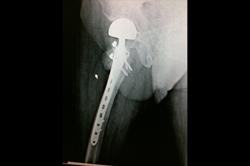

Periprosthetic Fracture THR